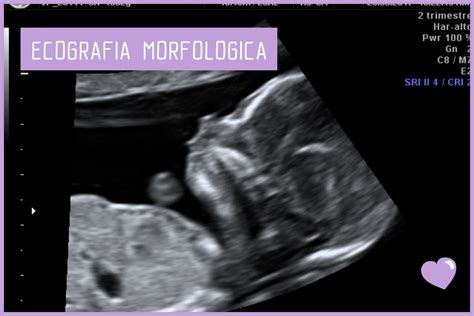

- Ecografia morfologica: Effettuata tra la 19esima e la 21esima settimana di gravidanza, rappresenta il metodo non invasivo standard per valutare l'anatomia fetale, inclusi gli organi genitali.

L’ecografia morfologica